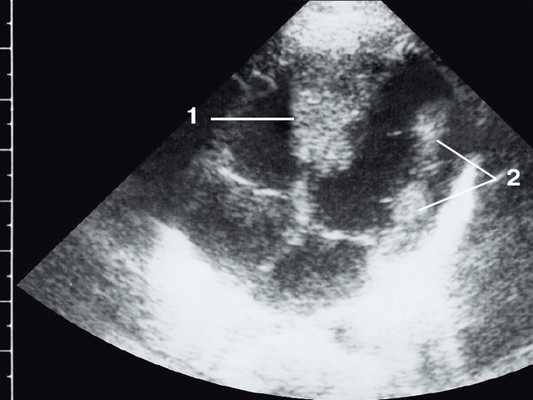

Рис. 1. Эхокардиограмма ребенка (девочки) с рабдомиомой. Крупный узел рабдомиомы в межжелудочковой перегородке (1) и менее крупные узлы в задней стенке левого желудочка (2). Эхоплотность образований выше, чем миокарда.

Рабдомиома сердца эхографически выглядят как достаточно четко очерченные образования. Чаще всего располагаются в миокарде левого желудочка, реже - в правом, еще реже - в предсердиях, кавоатриальных и атриовентрикулярных соединениях, эпикарде. Метастазирование не типично [8]. Наличие двух и более рабдомиом четко коррелирует с туберозным склерозом, одиночные рабдомиомы сердца такой связи, как правило, не имеют. По нашему опыту (18 пациентов), чем меньше объем новообразования, тем выше акустическая плотность, приближающаяся к эталонной эхоплотности (эндо-, эпи- и перикард). Эхоплотность больших рабдомиом практически не отличается от эхоплотности миокарда. В толще новообразования выявляются мелкие эхонегативные очажки (области некрозов) и эхопозитивные очажки (отложения кальция) (рис. 3).